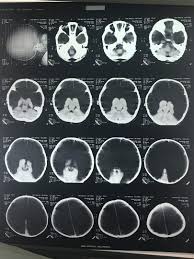

Vp shunt fracture. Ventriculoperitoneal vp shunts are a device used to shunt cerebrospinal fluid in the treatment of hydrocephalus. In follow up examinations we retrospectively reviewed patients who underwent revision surgery. Peritoneal catheter fractures occur most commonly in the neck the area where the tube is subject to mechanical stress.

The rate of shunt complications 1 month following insertion is 15 rising to 25 after 1 year and reaching 34 after 5 years 39 fig. Evidence based approach to complication prediction and avoidance during shunt surgery vp shunt surgery has a considerable long term complication rate. The shunt tubing is fractured at the level of the upper cervical spine.

Between 2006 and 2016 vp shunt surgery was performed on 1357 pediatric patients in our clinic. 5 6 the typical presentation of a fractured shunt system is usually quite late after initial insertion and it may be marked by the rapid onset of dramatic symptoms such as headache nausea swelling over the shunt tract often in a location over the shunt fracture or it may occur in a more subtle fashion over a longer period of time. As the name suggests a catheter is placed with its tip in the ventricle.

In follow up examinations we retrospectively reviewed patients who underwent revision surgery. The distal tubing is now coiled within the abdomen. Disconnection and fracture are two significant mechanical vp shunt dysfunctions and must be adequately researched and understood even during routine follow ups.

We have discussed the diagnosis and treatment approaches in patients with discontinued disconnected or fractured ventriculoperitoneal vp shunts that caused mechanical dysfunction. A disconnected or fractured shunt may be working and it is not safe to state that the shunt is no longer needed. Frontal radiograph of the cervical spine edge enhanced shows a fracture of the ventriculo peritoneal shunt drainage tube black and white arrows with caudal retraction of the distal fragment.

Between 2006 and 2016 vp shunt surgery was performed on 1357 pediatric patients in our clinic. 28097382 indexed for medline mesh terms. Ventriculoperitoneal vp shunt complications include blockage and infection early and prompt detection of shunt dysfunction is vital as delay can lead to markedly raised intracranial pressure coning and death.